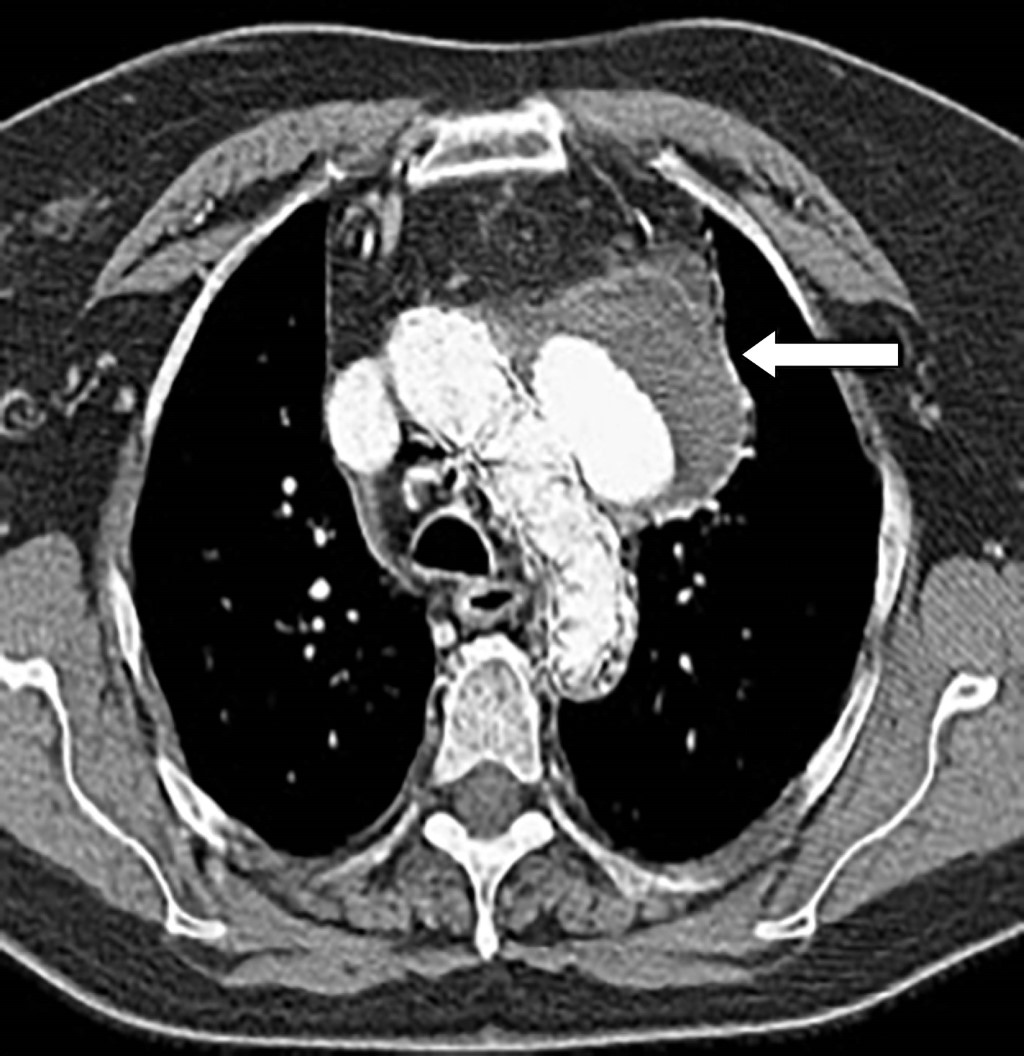

Figura 1